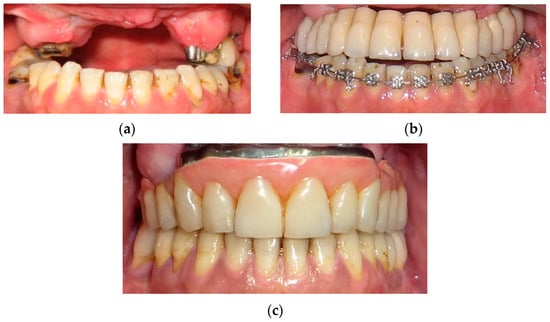

Figure 7.

A 46-year male patient with III dento-skeletal malocclusion and extensive IV Kennedy’s class, caused by myeloid leukemia: intraoral view before orthodontic surgery, without (a) and with temporary prostheses (b), and after surgery and rehabilitation treatment (c).